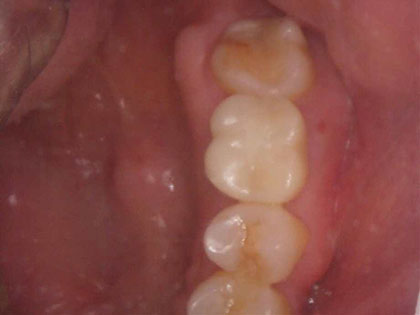

• 初診時の写真がこちら

• インプラント術前1

• インプラント術前2